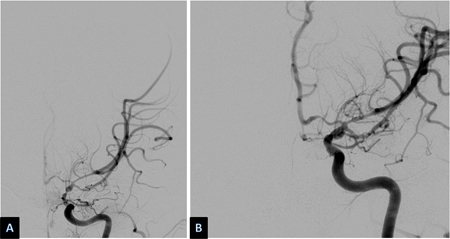

[Figure caption and citation for the preceding image starts]: Espasmo das artérias basilar e vertebral esquerdas distais antes (à esquerda) e depois (à direita) da infusão intra-arterial de nicardipinoCortesia do Dr. Salah Keyrouz; usado com permissão [Citation ends].

O efeito de compostos farmacológicos com formas de liberação controlada no vasoespasmo e no DIT tem atraído muito interesse. Implantes de nicardipino de liberação prolongada são colocados no espaço subaracnoide no momento da clipagem cirúrgica do aneurisma. Uma pequena série de casos e um ensaio clínico randomizado duplo-cego usando tais implantes relataram uma incidência de DIT menor que a esperada.[232][233][234][235]

Outros medicamentos usados em um sistema intracraniano de liberação controlada incluem a papaverina, o fasudil e doadores de óxido nítrico.[236] São necessários ensaios clínicos controlados mais amplos antes do uso disseminado dessa técnica. A papaverina, embora seja um vasodilatador historicamente efetivo, é geralmente evitada devido ao risco de neurotoxicidade.[37][237] O uso de agentes trombolíticos gotejados durante a cirurgia e/ou após a estabilização do aneurisma no espaço intratecal poderia ser benéfico. Eles eliminam o sangue do espaço subaracnoide necessário para o desenvolvimento do vasoespasmo. Uma metanálise concluiu que embora esses compostos pudessem melhorar o desfecho, os estudos analisados apresentavam limitações, incluindo um risco considerável de viés.[238] Outra intervenção que elimina o sangue do espaço subaracnoide é a drenagem lombar (DL) do líquido espinhal. Ensaios de DL mostram um benefício na incidência de vasoespasmo e ICT, mas nenhum efeito nos desfechos funcionais ou mortalidade em 6 meses.[239] Estudos sobre outras formas de administração intracraniana de nicardipino (intratecal, intraventricular e intracisternal) produziram resultados mistos. Na ausência de ensaios clínicos randomizados e controlados positivos, essas formas alternativas de administração intracraniana são reservadas para casos graves de vasoespasmo e ICT quando houve fracasso da terapia.[235]